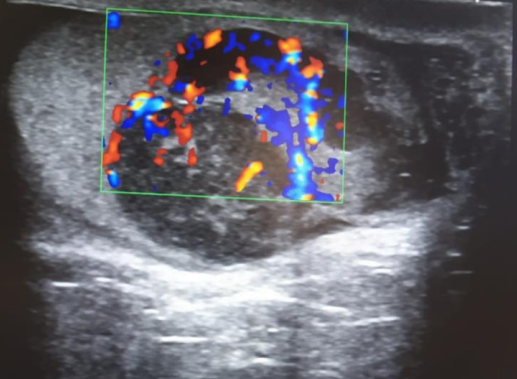

La ecografía (con doppler) informa de testículo derecho heterogéneo con múltiples áreas hipoecogénicas. Lesiones con marcada vascularización; compatibles con neoformación testicular derecha.

Ecografía del centro de salud: bultoma indurado y exofítico en polo inferior. Luminiscencia negativa. Áreas heterogéneas.